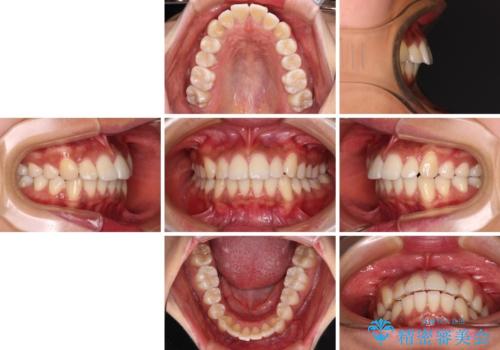

- 全体的な歯列の叢生を気にして来院された患者様です。

奥歯の咬み合わせを見ると、片方は上顎が下顎に対して相対的に前方にある状態でした。

咬み合わせを改善するためには、上顎臼歯を後方に移動させた咬み合わせにする必要があります。

インビザライン単体で改善することも可能ですが、ディープバイトのためインビザライン単体で達成する可能性が低いと考えられたため、カリエール・ディスタライザーという補助装置を併用して、より確実性を上げることとしました。

奥歯の咬み合わせ改善後に、インビザラインにて歯列を整えることとしました。

カリエールディスタライザーを併用したことで、確実かつ短期間で治療を終えることができました。